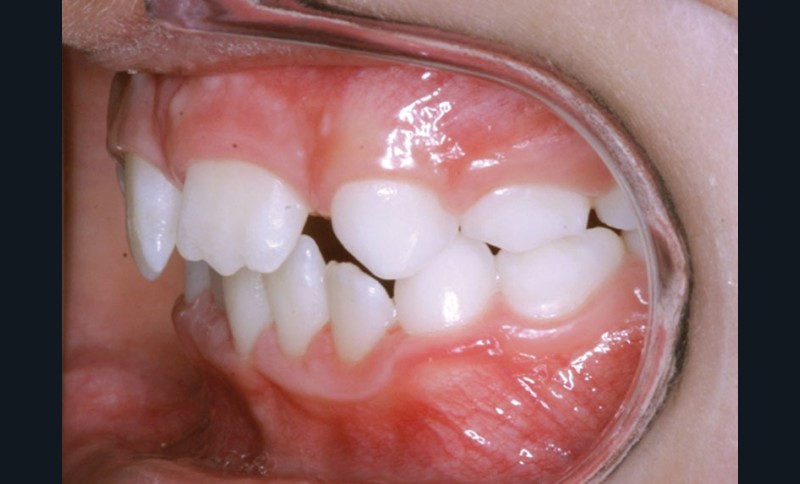

La décision thérapeutique s’est orientée dès cette consultation vers la fermeture des espaces d’agénésie et l’extraction de la 52 a été réalisée à ce stade pour respecter la symétrie antérieure et favoriser l’évolution symétrique des deux canines en position d’incisives latérales.

Les vues endo-buccales après extraction de 52 montrent des relations occlusales de classe II, un léger encombrement incisif mandibulaire et une tendance à la fermeture spontanée des espaces des incisives latérales confirmant le choix thérapeutique d’une fermeture d’espace (fig. 2).